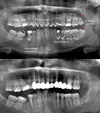

أمراض الأسنان واللثة

التهاب ما حول الزرعة

التهاب مخاطية ما حول الزرعة